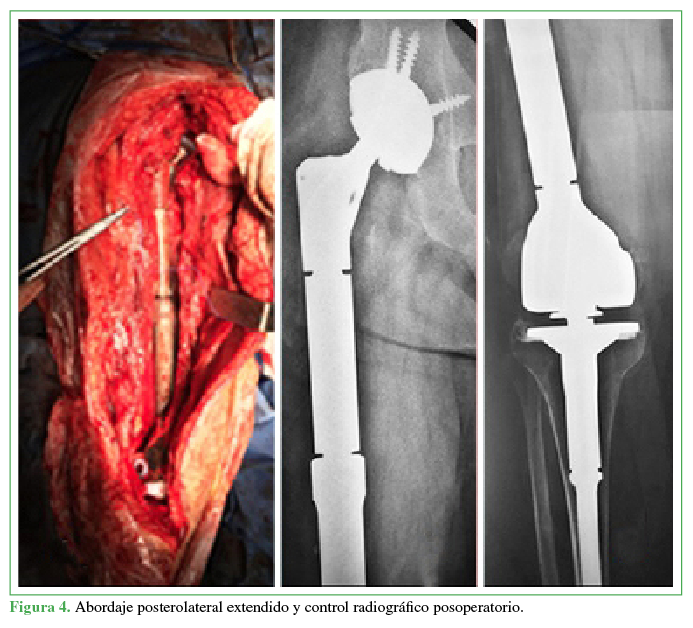

La evolución posoperatoria a corto plazo fue mala, con osteosíntesis fallida asociada a imágenes heterogéneas y líticas difusas a nivel diafisario (Figura 1).

Figura 1

Evolución radiográfica de la primera intervención quirúrgica.

Figura 4

Abordaje posterolateral extendido y control radiográfico posoperatorio.